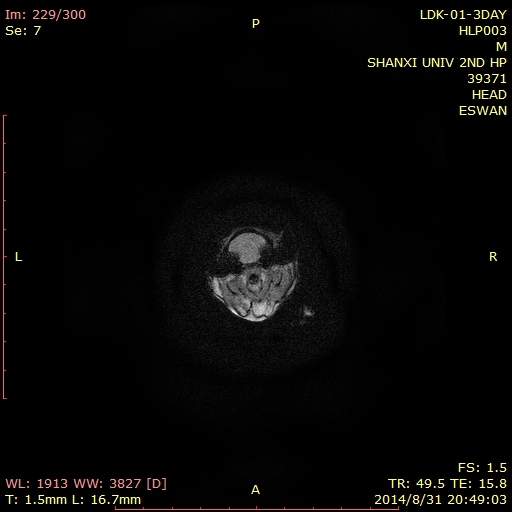

Matlab 7.0怎么处理swan图像得到幅度信号值、相位值。高人请进!